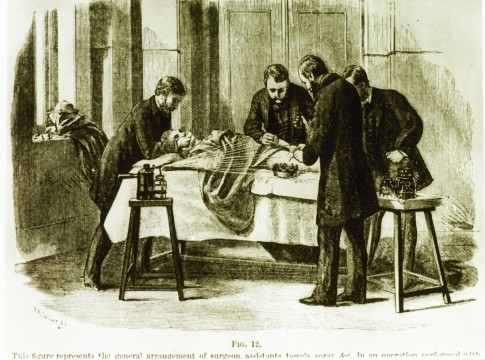

1846年11月18日

波士顿的外科医生Henry Jacob Bigelow,让病人吸入乙醚进行麻醉。这个技术后来运用到各种手术中,从拔牙到截肢。

1867年

英国外科医生Joseph Lister倡导手术操作时要消毒。他注意到接生婆接生的新生儿的死亡率比外科医生接生的要低,他将这点归功于接生婆比外科医生洗手更频繁。他提出外科医生不仅需要用石炭酸洗手,还要消毒手术器械。这些是微生物理论提出的起源。